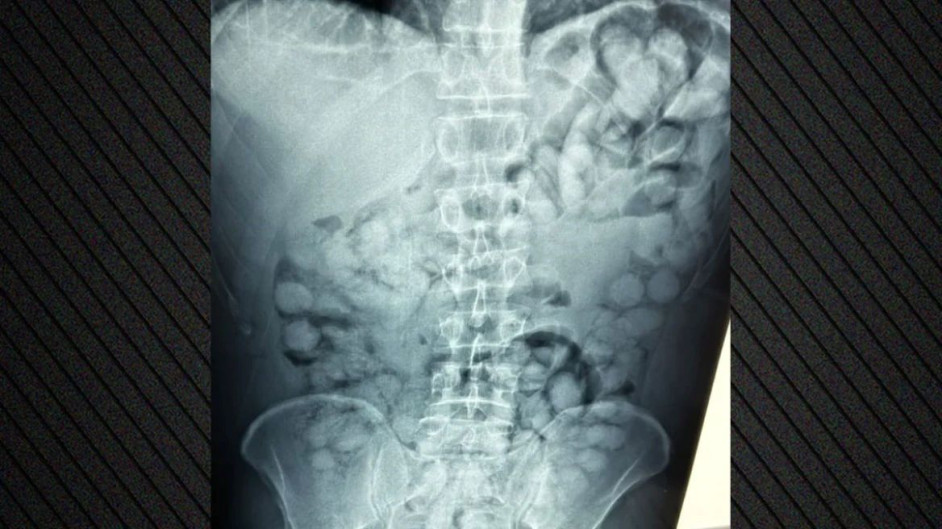

Όπως ανακοίνωσε η ΕΛ.ΑΣ., ο συλληφθείς είχε φτάσει στην Αθήνα μέσω Παρισιού και κατά τον έλεγχο διαπιστώθηκε ότι είχε καταπιεί περίπου 100 μικροδέματα της ναρκωτικής ουσίας.